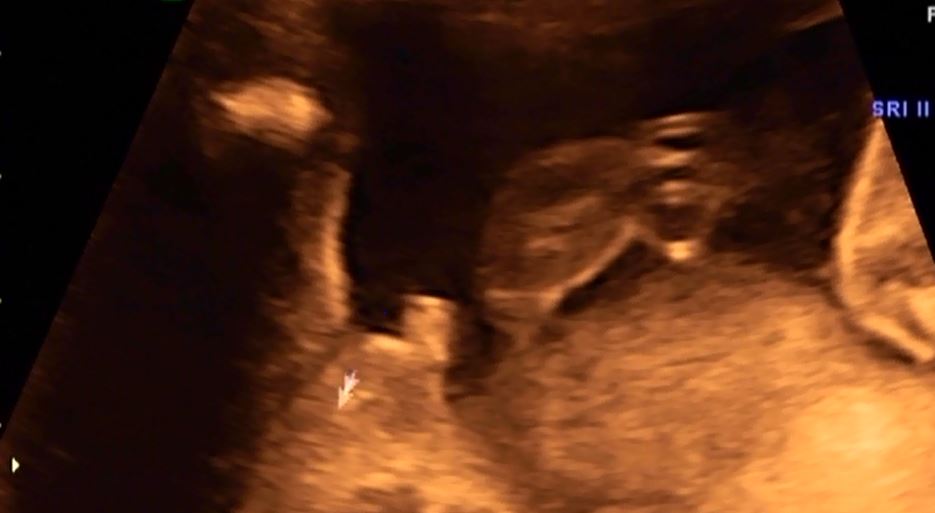

Przedstawiam Jana :D na ostatnim zdjęciu wiecie co... :D